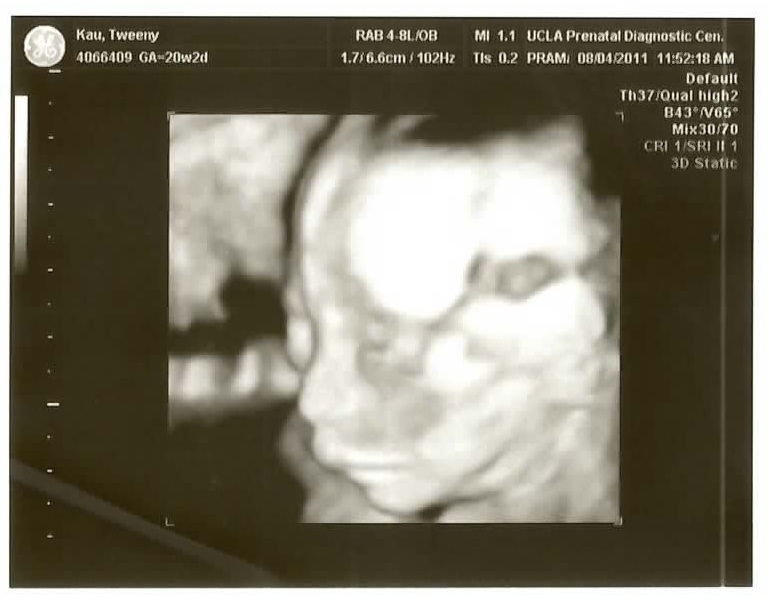

We just went back for our twenty week checkup/ultrasound and as usual they gave us a DVD which I have ripped to YouTube (it’s just everything they did.. 17:10 long.. I cut out the first 2:20 of the intern bumbling around to keep it under the 15 minute YouTube maximum).

See if you can figure out what gender it is from the ultrasound pics! Check the comments for the answer!

The 3D pictures are kind of funny because the ultrasound technicians are all like “So CUTE!” and all I can think is “for a pig face!” The one face-on isn’t so bad if you don’t look above the bottom lip I guess..